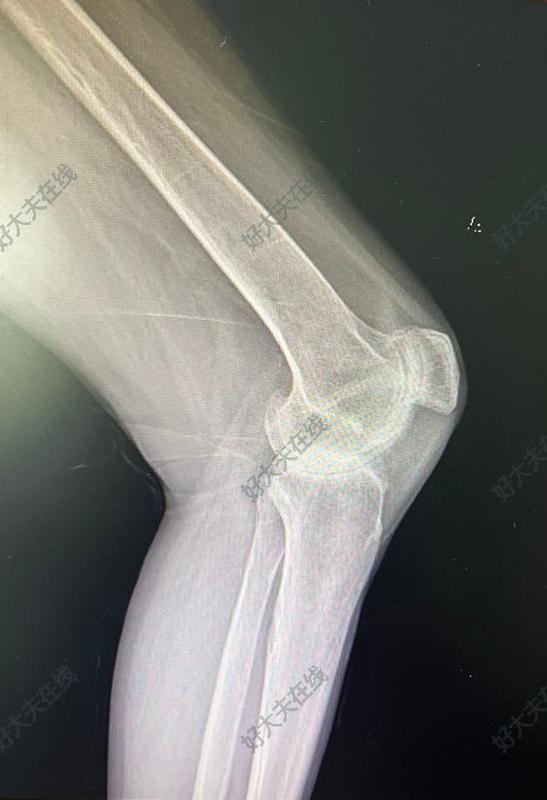

治療前患者類風濕性關節(jié)炎,膝關節(jié)活動受限明顯,不能伸直,不能屈曲活動。疼痛明顯影響生活。走路跛行嚴重。X光片顯示關節(jié)間隙狹窄消失,骨質疏松明顯。治療后治療后即刻使用機器人輔助手術技術,假體安放位置精準,韌帶平衡合適,畸形完全糾正,手術后膝關節(jié)可以伸直,彎曲活動滿意。手術后第二天可以在助行器保護下地活動走路。明顯改善關節(jié)功能。